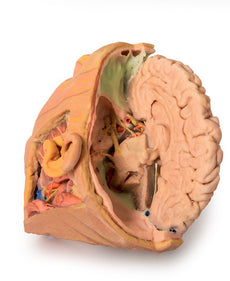

3D Printed Brain Hemisection

This 3D model is a midsagittal hemisection through a whole brain, preserving the right side anatomy and deep brain

structures and spaces visible in the midline. In lateral view, the right cerebral and cerebellar hemispheres are

covered in the arachnoid mater. In the midline view, the brain regions from the cerebrum to the medulla oblongata

are preserved. Centrally, the third ventricle is opened, with an intact septum pellucidum superiorly positioned and

obscuring the lateral ventricles within the cerebral hemisphere. On the inferior margin of the third ventricle both

the right mamillary body and right optic tract can be observed, whereas posteriorly the cerebral aqueduct can be

observed extending across the midbrain between the tectum and tegmentum towards the fourth ventricle (between the

cerebellum and pons). The cerebellum is separated from the occipital lobe by a preserved portion of the tentorium

cerebelli, and in cross-section the cerebellar cortex helps form the prominent arbor vitae.

A series of arterial

branches have been false coloured to contrast their course across the preserved brain structures. In the midsagittal

view the anterior cerebral artery courses from around the corpus callosum to supply the cingulate gyrus and other

midline cortical regions. The base of the middle cerebral artery can be seen passing deep between the temporal and

frontal lobes, with the posterior communicating artery connecting it to a small remnant of the posterior cerebral

artery. Adjacent to the posterior cerebral is the superior cerebellar artery, extending laterally to pass between

the temporal lobe and the cerebellum before passing deep into the transverse fissure.